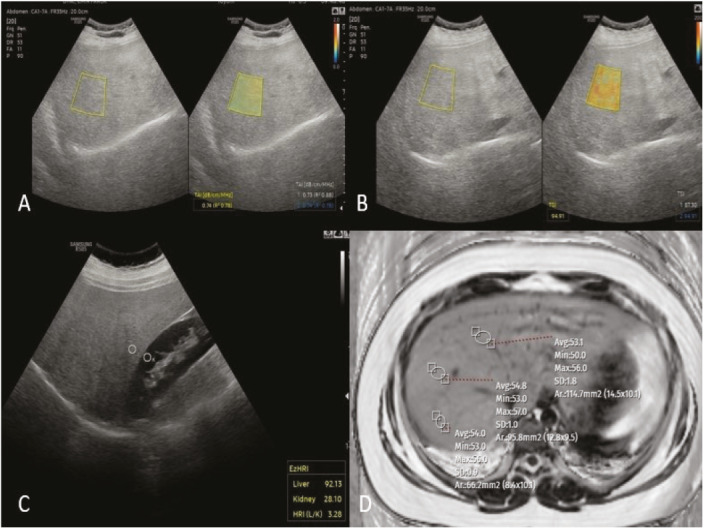

Methods: The study group consisted of pediatric patients under 18 years of age without known liver disease who volunteered to participate. All patients underwent MRI-PDFF scanning, and QUS imaging was performed using the tissue attenuation imaging (TAI) ve tissue scatter distribution imaging (TSI) tools. The cut-off values for MRI-PDFF were set at ≥5%, ≥16.3%, and ≥21.7%, corresponding to mild, moderate, and severe steatosis, respectively. The diagnostic performance of TAI and TSI in detecting various degrees of hepatic steatosis was evaluated using the area under the ROC (AUROC) curves.

Results: The frequencies of hepatosteatosis grading were as follows: S1: 19 (37%), S2: 5 (10%), S3: 22 (43%). The AUROCs for TAI and TSI tools in detecting QUS measurements (MRI PDFF ≥5%) were 0.95 [95% confidence interval (CI): 0.91-0.99] (p< 0.001) and 0.96 (95% CI: 0.93-0.99) (p<0.001), respectively. For distinguishing different degrees of steatosis, TAI showed values of 0.75, 0.86, and 0.96 dB/cm/MHz, corresponding to sensitivities of 88%, 88%, and 100%, respectively, while TSI showed values of 92.44, 96.64, and 99.45, with sensitivities of 90%, 92%, and 91.7%. The correlation test between QUS measurements [TAI, TSI, EzHRI (Hepato-Renal Index with Automated regions of interest Recommendation)] and MR-PDFF indicated a concordance in TAI and TSI values, but not with EzHR.

Conclusions: The TAI and TSI tools can accurately measure liver fat content and can be used reliably in children for the assessment and grading of hepatosteatosis.